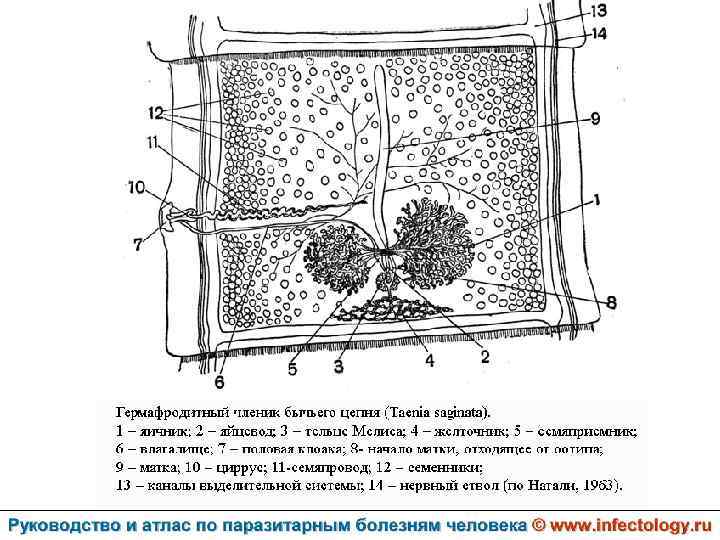

Тениаринхоз (шифр по МКБ 10 - B 68. 1) – антропонозный биогельминтоз с хроническим течением, характеризующийся преимущественно желудочно– кишечными расстройствами.